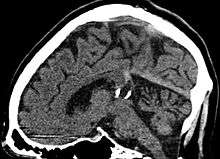

Pineal gland cyst

A pineal gland cyst is a usually benign (non-malignant) cyst in the pineal gland, a small endocrine gland in the brain. Historically, these fluid-filled bodies appeared on 1-4% of magnetic resonance imaging (MRI) brain scans, but were more frequent at death, seen in 21-41% of autopsies.[1] A 2007 study by Pua et al. found a frequency of 23% in brain scans (with a mean diameter of 4.3 mm).[1]